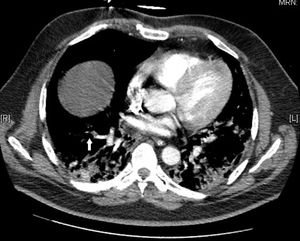

Estudio de la situación: a nivel pulmonar, en la radiografía de tórax destaca patrón alveolointersticial pulmonar bilateral respetando ambos vértices pulmonares, compatible con neumonía por COVID-19 (fig. 1). En la TAC torácica (realizada el 10.° día de ingreso en la UCI) se aprecia dudoso defecto de repleción en rama segmentaria del lóbulo inferior derecho (LID), opacidades pulmonares parcheadas en vidrio deslustrado y pequeñas consolidaciones bilaterales difusas, con engrosamiento de septos interlobulillares en lóbulo inferior izquierdo (LII), en relación con neumonía por COVID-19, informándose como posible TEP periférico en LID y hallazgos compatibles con COVID-19 (fig. 2)6.